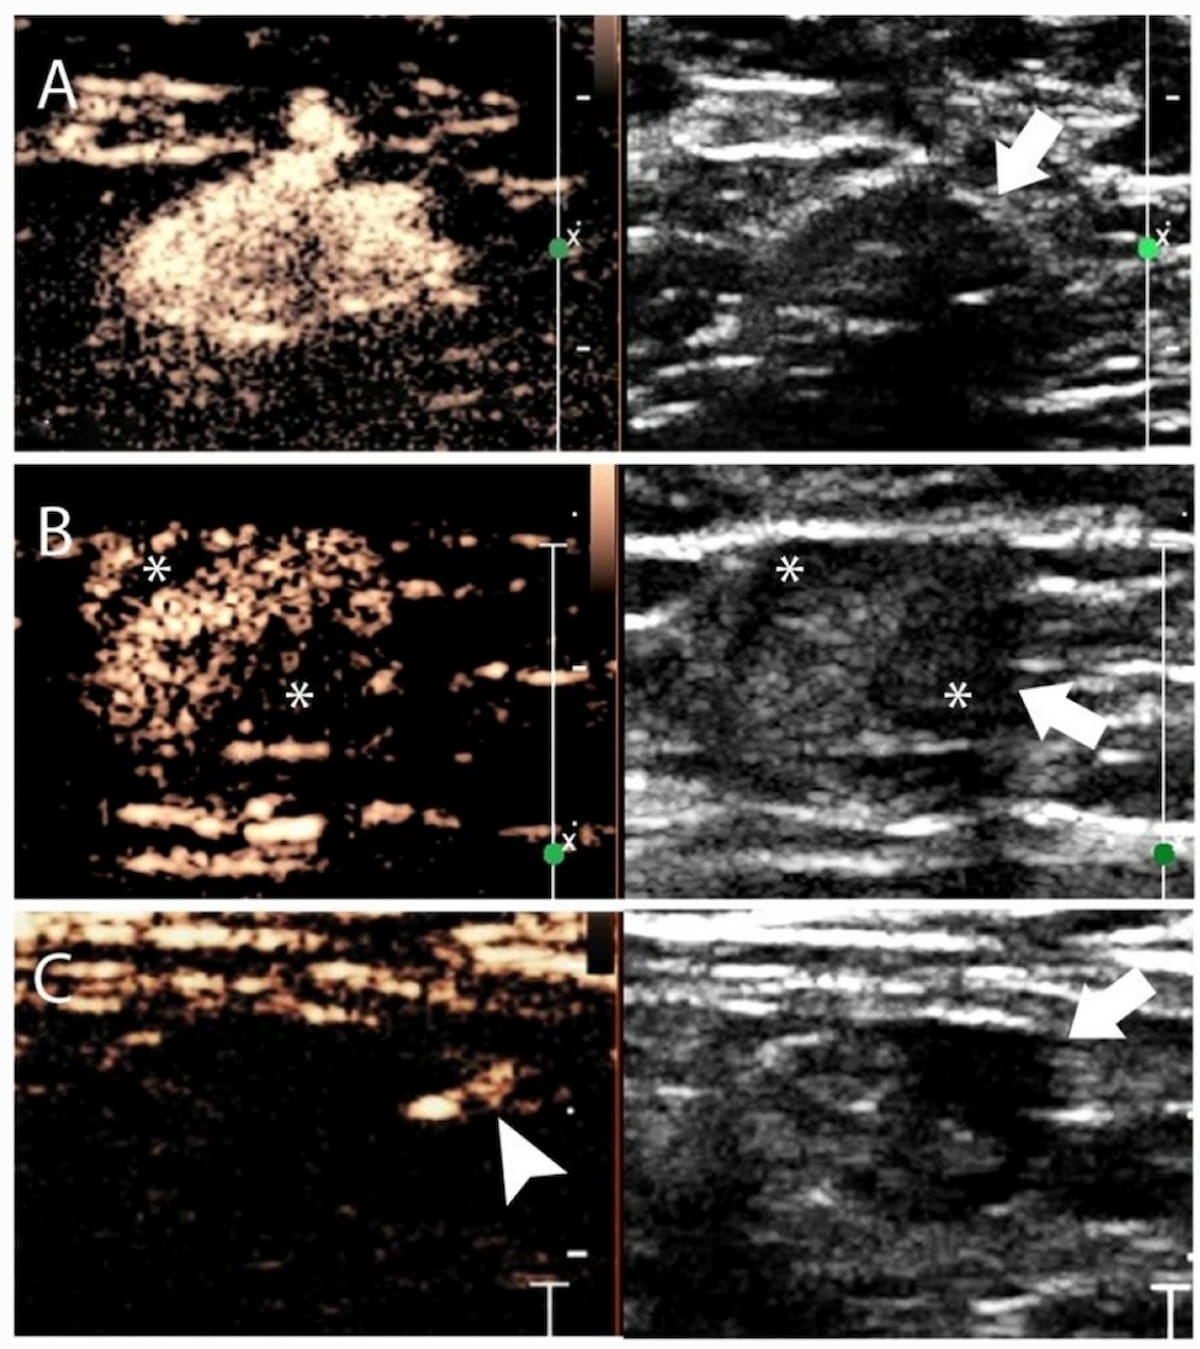

In a comparison of image-to-text large language models (LLMs), ChatGPT 4.0 offered a 95 percent sensitivity rate and an 83 percent AUC that were comparable to that of two senior radiologists and one junior radiologist interacting with LLM to differentiate between malignant and benign thyroid nodules on ultrasound.